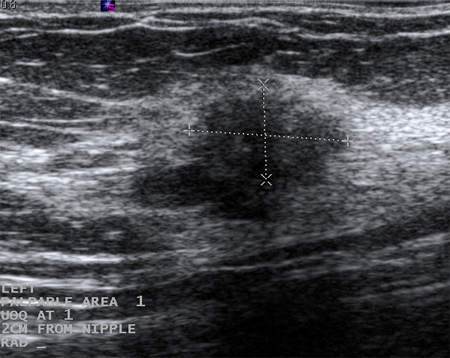

Massa palpável com envolvimento de pele na mama esquerda

Cortesia da Drª Anees Chagpar